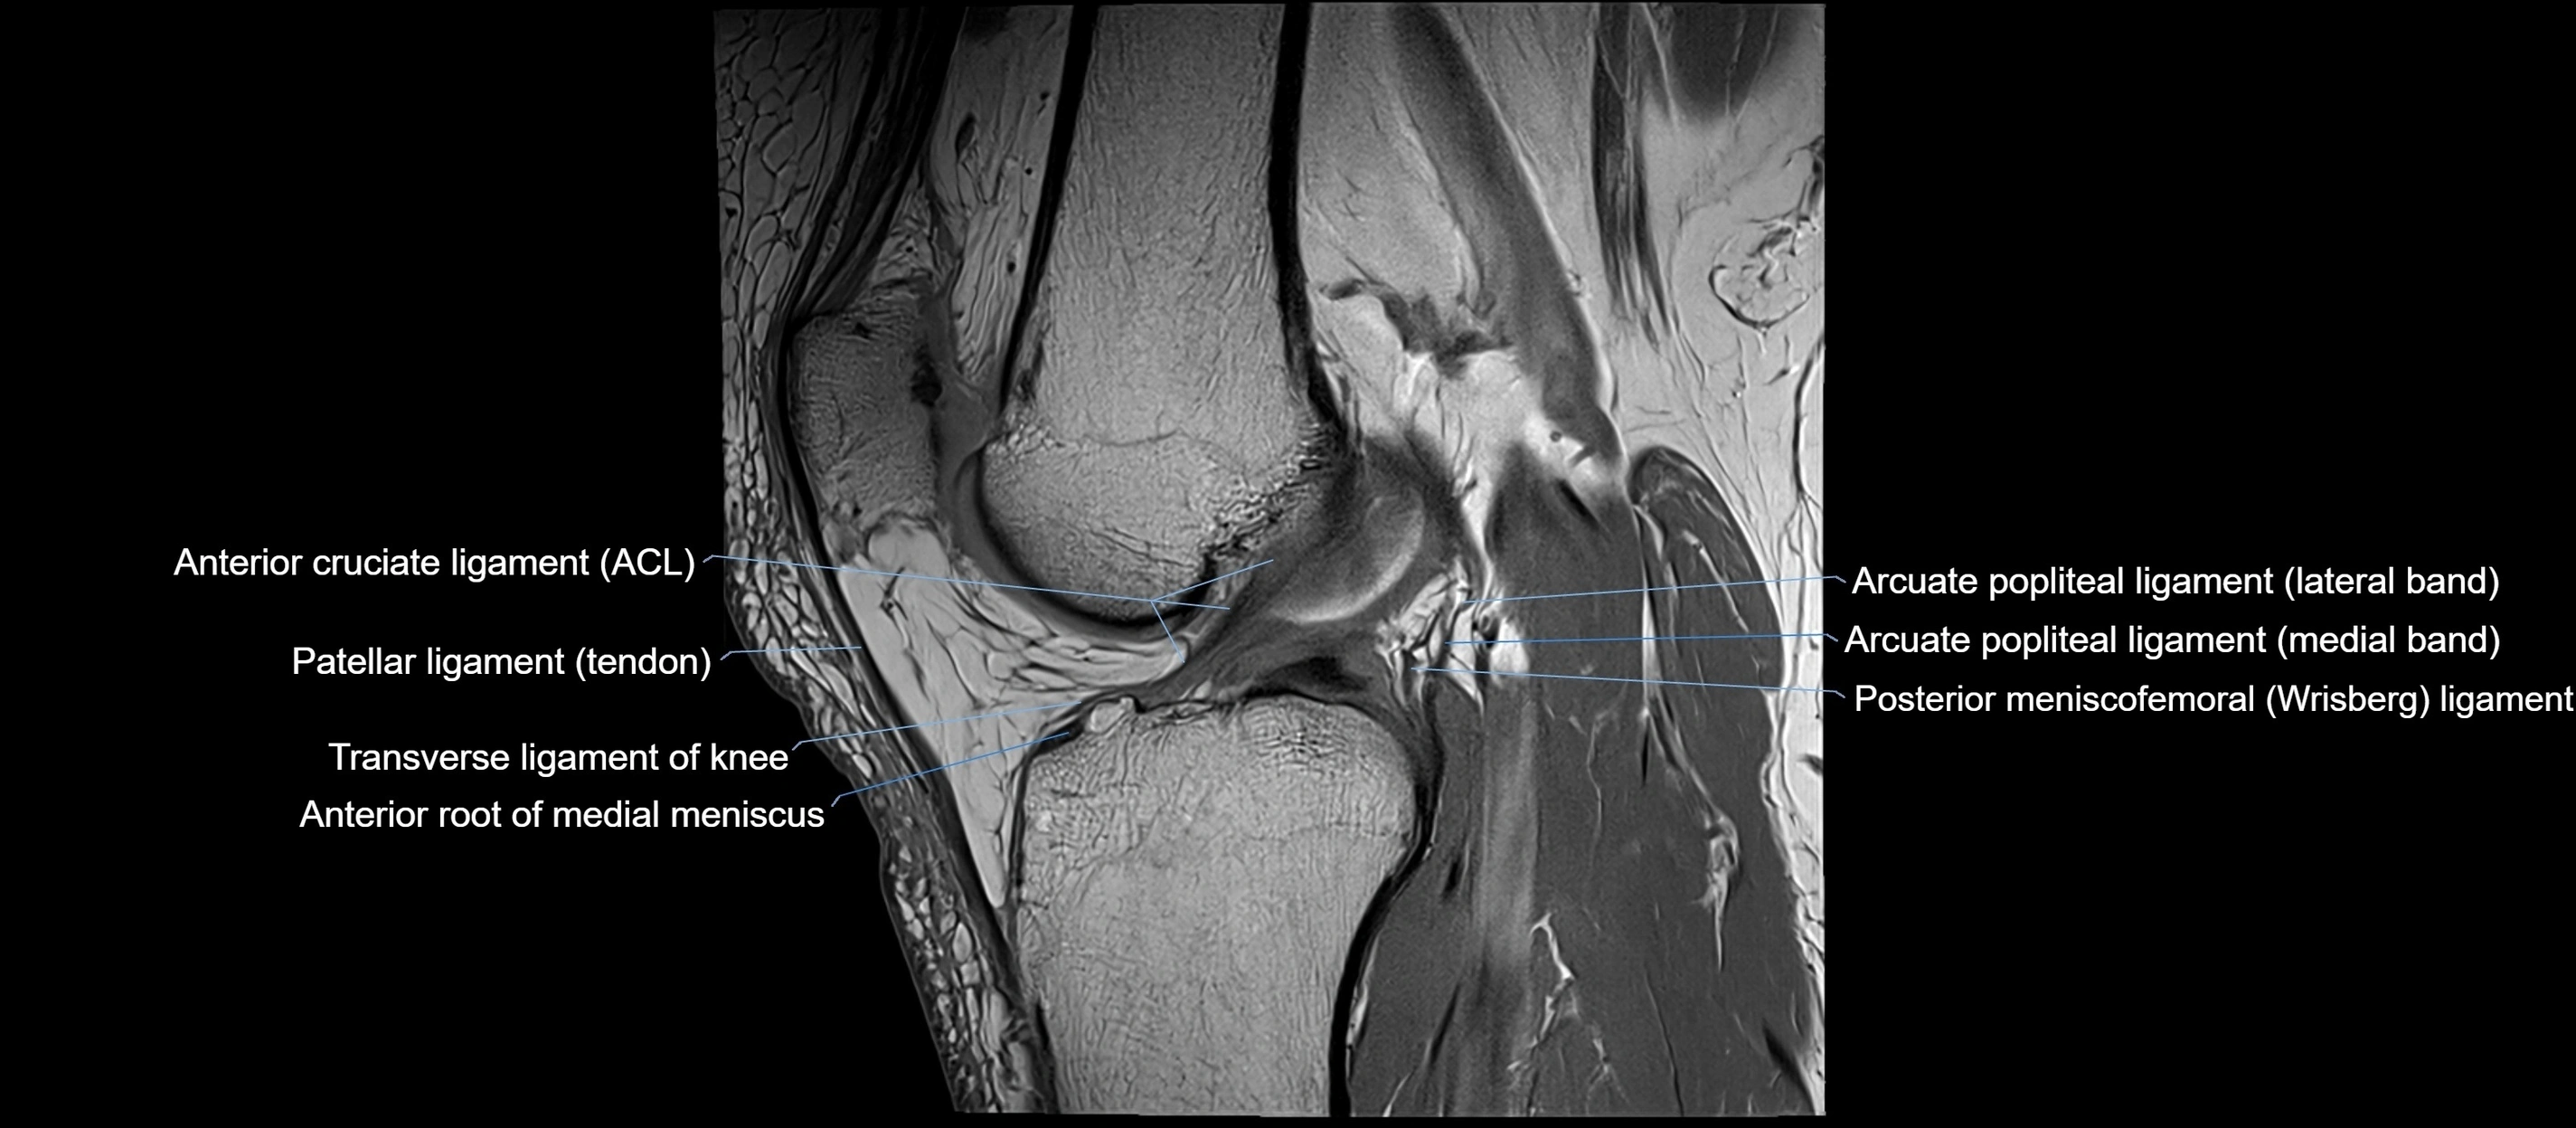

MRI images

image

MRI Appearance

T1-weighted images:

• Normal ACL appears as a low-signal band-like structure crossing the intercondylar notch

• Surrounded by intermediate signal synovial fluid and fat planes

T2-weighted images:

• Normal ACL remains low signal

• Partial or complete tears appear as discontinuity, increased signal, or fiber laxity